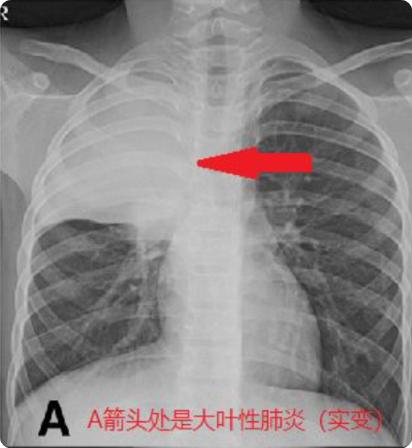

从去年延续至今的儿童肺炎支原体感染一直居高不下,期间再交替出现的流行性感冒病毒、腺病毒等等,各种呼吸道感染病原轮番上阵,不少孩子不幸中招罹患肺炎,而其中出现大片肺实变、肺不张者非常常见,重症肺炎者也不乏少数,甚至有“白肺”的发生,这样的孩子在常规的肺炎治疗基础上,应该如何更好地肺康复呢?

哪些儿童需要接受肺康复?①常见的呼吸系统疾病:大叶性肺炎、肺不张、闭塞性支气管炎、闭塞性细支气管炎、间质性肺疾病、支气管扩张、囊状纤维化、原发性纤毛运动障碍、支气管哮喘等;